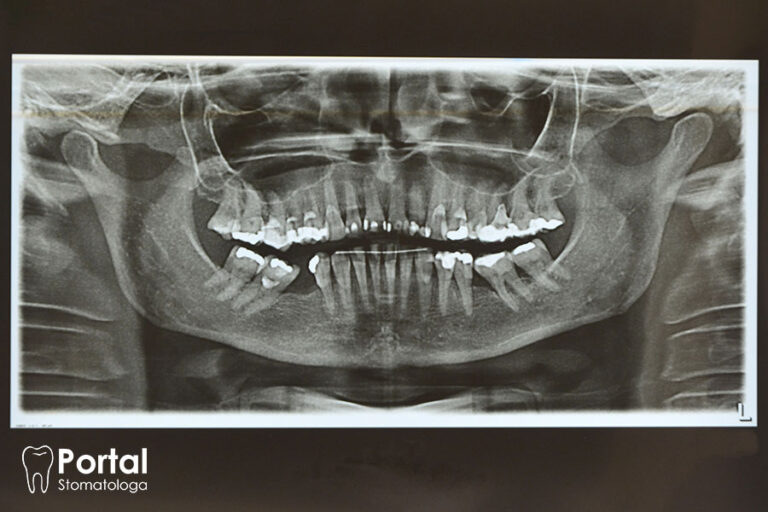

- wady zgryzu, w tym obecność zębów nadliczbowych;

Wstępne rozpoznanie ustala się na podstawie obrazu klinicznego. Często już po samym wyglądzie lekarz może stwierdzić, że u młodego pacjenta rozwinęła się kraniosynostoza. Nie jest jednak w stanie stwierdzić, która jest to choroba z tej grupy. Dlatego wykonuje się badania genetyczne oceniające gen TWIST1 bądź FGFR3. Jest to badanie molekularne, do którego wykonania niezbędna jest próbka krwi obwodowej lub wymaz z jamy ustnej. Cena takiego badania wynosi niecałe 400 zł, a wyniki dostępne są w ciągu 2 tygodni.